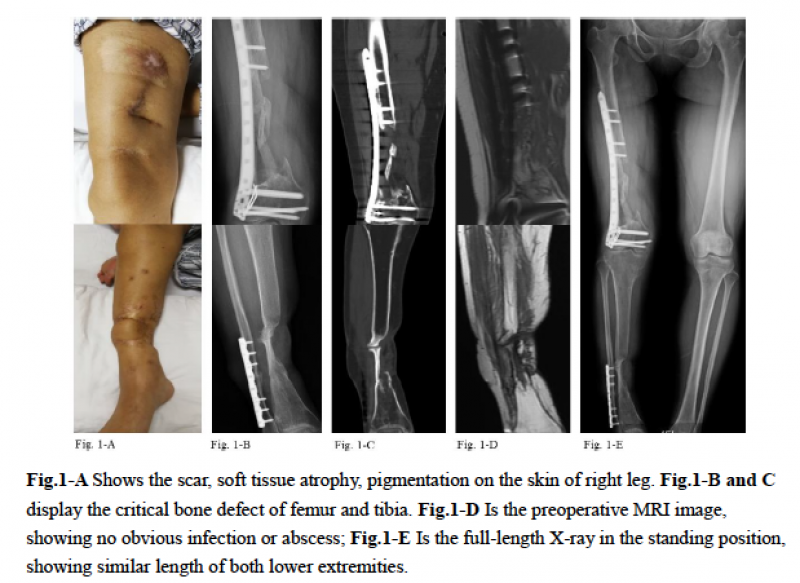

典型病例:姜某,女性,41岁,主因“右下肢骨折术后3年余,发现骨不连3个月”入院。

治疗过程:结合查体、化验检查等资料,除外感染性骨不连,遂决定行分期手术治疗。

一期:彻底行瘢痕组织及硬化骨切除,在缺损区填充骨水泥Spacer,留置引流。术后拔除引流管后对双下肢进行三维CT扫描,通过医工结合进行3D打印假体设计及制备。

图1: 患者入院影像学检查